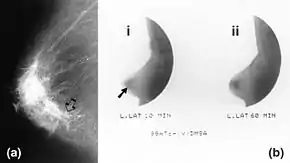

|  Mammography (left) and DMSA scintimammography (right) images of 4.5cm breast carcinoma | |